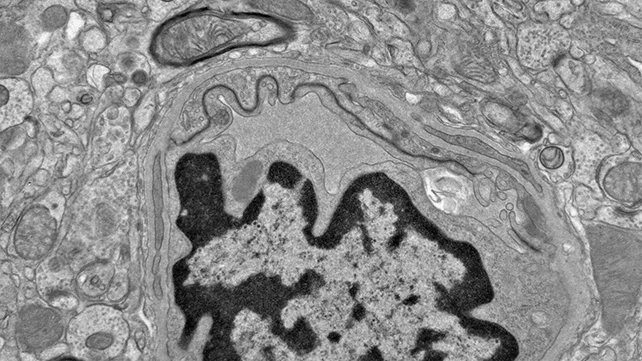

تجارب الفريق البحثي على خلايا بطانية دقيقة مشتقة من دماغ بشري أظهرت أن حمض “دوكوساهيكسانويك” (DHA) لم يعرقل الإصلاح. في المقابل، تراكم حمض EPA في أدمغة الفئران المصابة وتسبب في زعزعة استقرار الأوعية الدموية. هذا التراكم ارتبط بظهور بروتينات “تاو” السامة، وهي علامة حيوية معروفة بارتباطها بتنكس الدماغ. تحليلات إضافية لأنسجة دماغية بشرية مصابة باعتلال الدماغ الرضحي المزمن (CTE) كشفت عن اضطرابات أيضية وتلف وعائي يشبه النتائج المرصودة في تجارب الفئران.